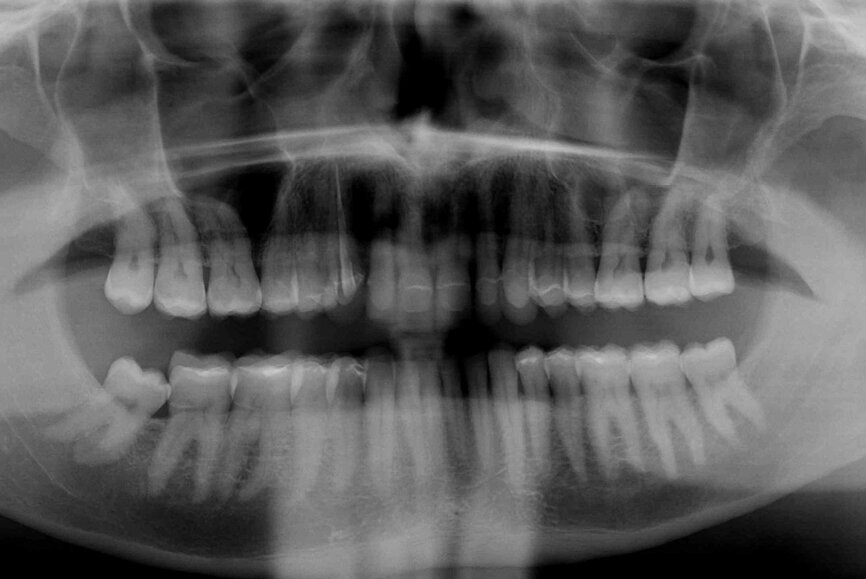

In 2015, a 47-year-old male patient presented complaining of pain in the TMJ. He also had an aesthetic request, since part of the veneer on one of the maxillary central incisors had broken off (Figs. 1–3). The clinical and radiographic analysis (Fig. 4) indicated a loss of bite height and tooth substance due to bruxism.

Fig. 4: Initial situation, panoramic radiograph (2015).